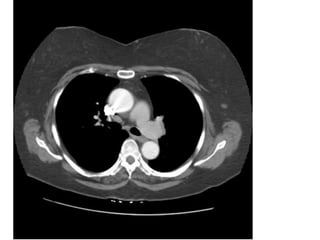

Figure 9. PE ở bn nữ 42 tuổi, đau ngực và khó thở nhiều.

- Hình ảnh thất phải dãn lớn hơn thất trái.